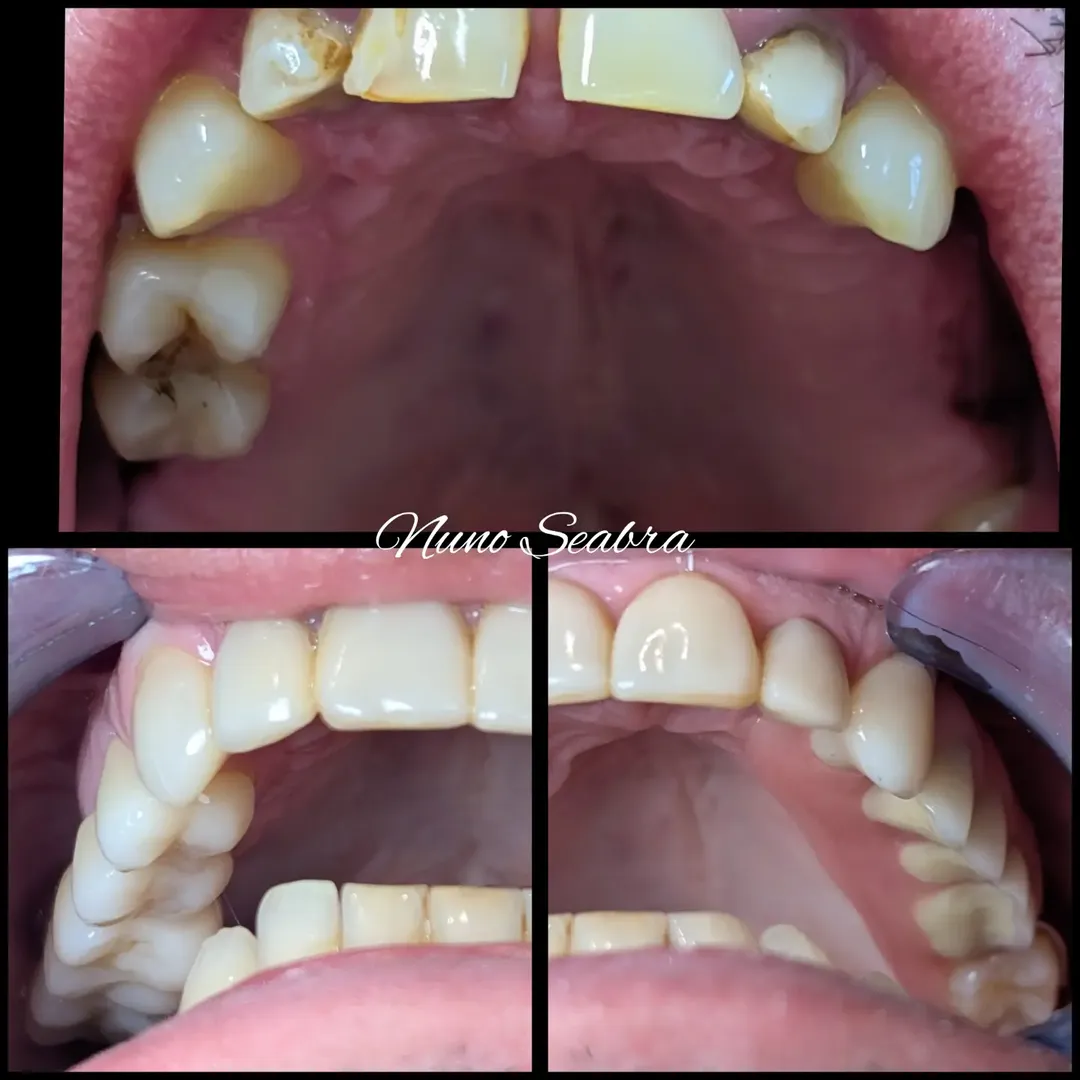

- Setor anterior - Facetas em resina composta: Para devolver a harmonia estética ao sorriso, apliquei facetas diretas em resina composta nos dentes anteriores, corrigindo forma, cor e alinhamento.

Resultado

Nas imagens, é possível ver a evolução desde a situação inicial com múltiplas ausências e dentes comprometidos, até ao resultado final com todas as zonas reabilitadas. O paciente recuperou a função mastigatória completa e uma estética natural, sem ter de usar uma prótese removível.

Este caso demonstra que nem sempre precisamos de implantes em todas as zonas para alcançar um bom resultado. Saber combinar pontes fixas, implantes onde há osso disponível, overdentures de encaixe e facetas estéticas permite resolver casos complexos de forma integrada, respeitando as limitações anatómicas e as preferências do paciente.